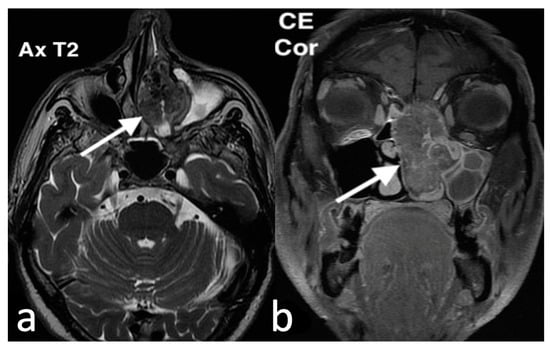

3.3.2. Esthesioneuroblastoma